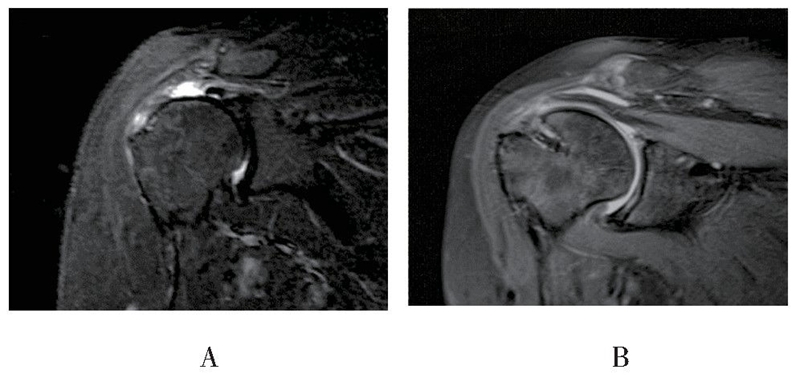

MRI随访见18例患者重建组织结构完整,愈合率达85.7%(18/21),3例出现明显结构失败,但失败患者功能恢复良好,未诉明显不适,因此未行翻修手术(见图5、图6)。

图5 患者女,67岁,末次随访时斜冠状位MRI显示右肩术后重建结构连续性完整A:术前磁共振影像,B:术后磁共振影像